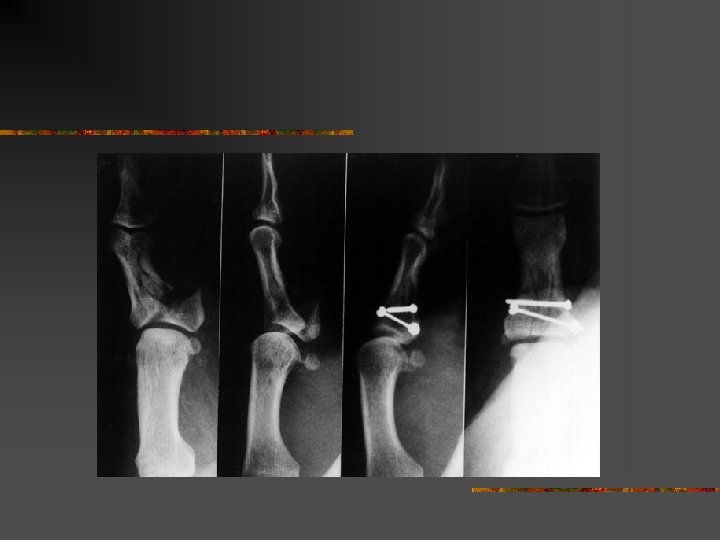

Fracture de Bennet n n Traction du long abducteur du pouce Déplacement inéluctable

Mécanismes déplacements n n Métacarpiens Phalanges : P 1 et P 2 Fracture de Bennet = base de M 1 Fracture de la base du 5 eme métacarpien

Méthode de traitement n n n Mobilisation immédiate = Tt fonctionnel Traitement orthopédique = immobilisation Traitement chirurgical = n n n Broches Vis et plaques Fixateur externe

Traitement n Chirurgical : n n n Abord chirurgical de l’articulation Réduction sous contrôle de la vue Stabilisation par broche